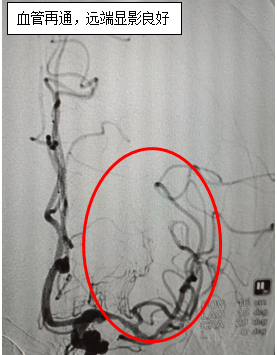

神经内科介入团队立即行动,通过全脑血管造影检查,发现患者大脑中动脉血栓影,远端显影延迟、浅淡,急诊行颅内动脉取栓术,经过3小时努力成功将血栓取出,闭塞的动脉及动脉远端血流恢复通畅,成功救治了患者,术后患者神志恢复、肢体力量完全恢复。

时间就是大脑,时间就是生命,时间更是这位患者的未来,必须争分夺秒!与家属充分沟通后予以桥接治疗,随即,神经内科介入团队行脑血管介入开通治疗。手术顺利结束后转重症监护室治疗,术后恢复稳定,并康复出院,避免家庭负担,回归社会。该项神经介入技术标志着我院在卒中急诊急救方面实现了里程碑式突破。